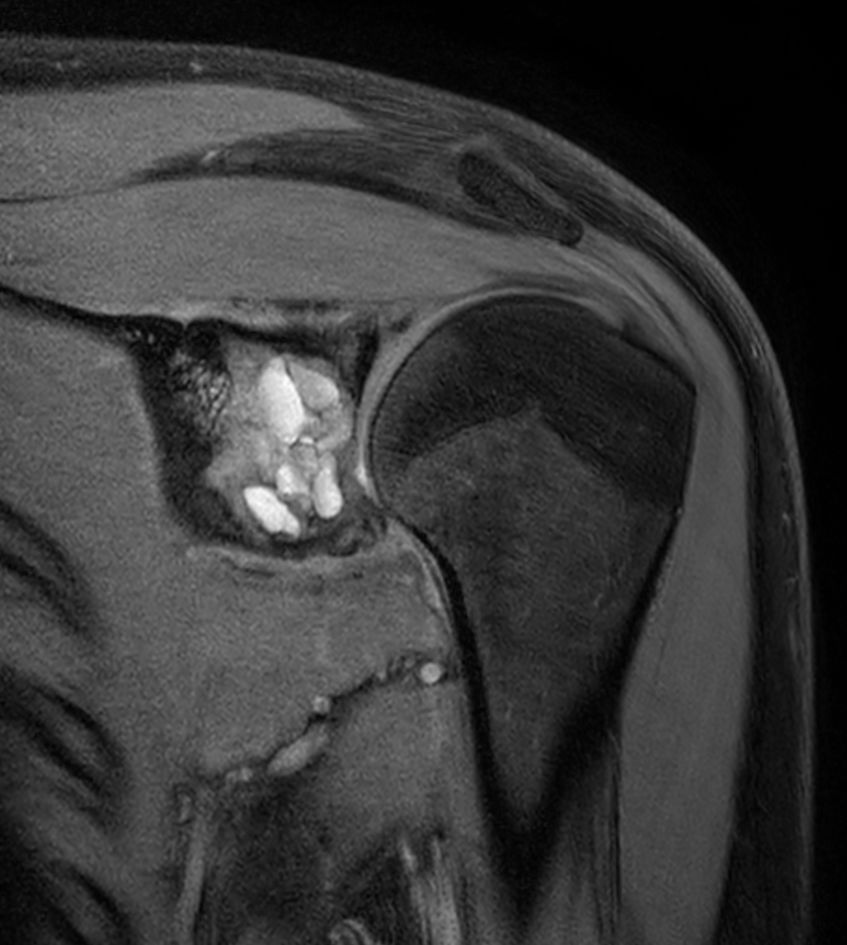

Coronal T1w mDIXON XD TSE - Compressed SENSE (Water only)

Coronal T1w mDIXON XD TSE - Compressed SENSE (In Phase)

Coronal T1w mDIXON XD TSE - Compressed SENSE (Water only) - Post-gado

Coronal T1w mDIXON XD TSE - Compressed SENSE (In Phase) - Post gado